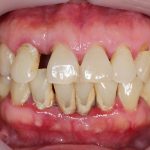

Gejala Periodontitis

Gejala periodontitis bisa beragam dan tergantung pada perkembangan peradangan yang terjadi gusi dan gigi. Namun, ada beberapa gejala atau keluhan yang umum dialami oleh penderita periodontitis, yaitu:

- Penumpukan plak dan karang pada gigi

- Gusi menyusut sehingga membuat gigi terlihat lebih panjang

- Gusi berwarna kemerahan atau keunguan

- Gusi bengkak dan mudah berdarah